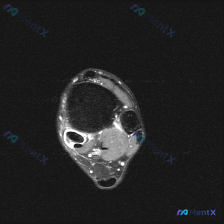

看到一份踝关节MRI的读片资料,整理了完整的分析和鉴别思路分享给大家。 病例核心影像信息 这是踝关节上方水平的轴位T2序列MRI: 1. 解剖层面:显示踝穴上方的胫骨远端干骺端、腓骨远端,可清晰识别跟腱、胫骨后肌腱、趾长屈肌腱、踇长屈肌腱、腓骨长短肌腱等结构 2. 核心阳性发现:内踝后方胫骨后肌腱的...